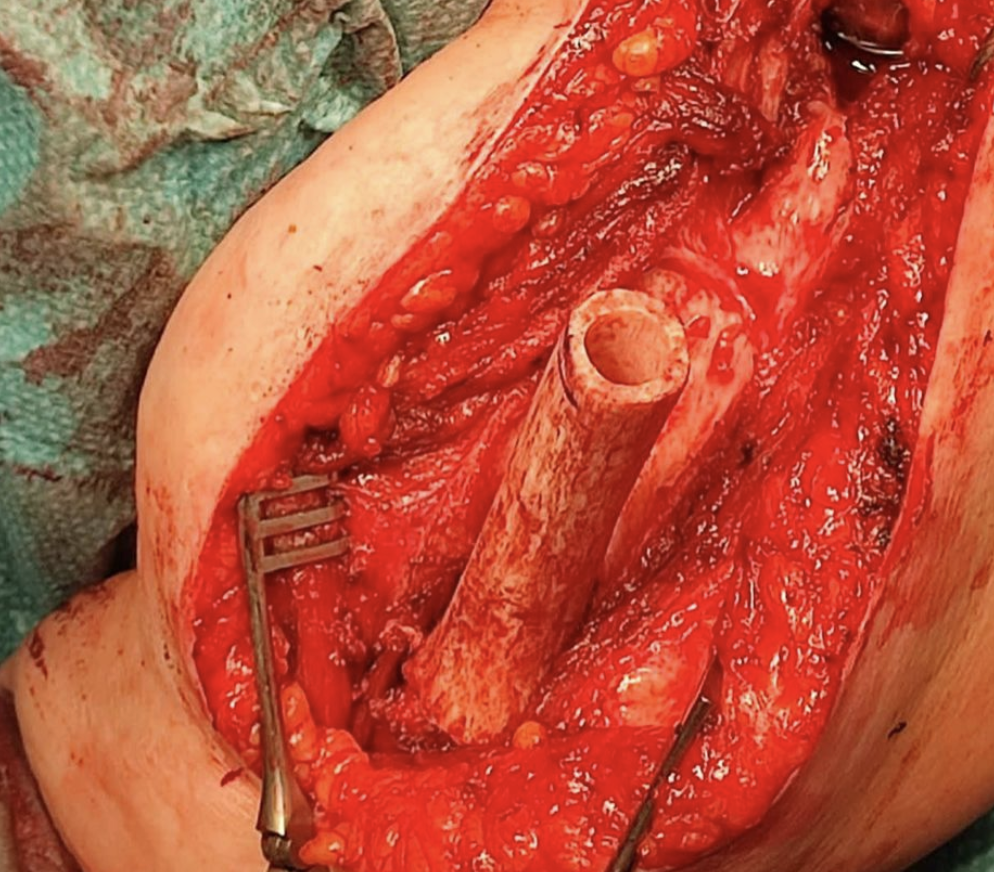

Condrosarcoma en húmero

Hoy me gustaría compartir el caso de una mujer de 72 años con un condrosarcoma G3 de humero izquierdo (imágenes 1,2),  a quien hace 1 año se le realizó una resección (imagen 3) y reconstrucción con la megaprótesis invertida Comprehensive SRS cementada de Zimmer Biomet. (imagen 4) Radiografía de control (5). A los 6 meses presenta un aflojamiento aséptico (imagen 6). Retiramos el componente humeral (imagen 7) y reconstruimos con un ALOINJERTO TELESCOPICO PRESSFIT (imagen 8) y un nuevo componente humeral mas corto (imagen 9) Radiografías de la reconstrucción AloProtésica (imagen 10)

Para poder ayudar a los pacientes con sarcomas debemos tener múltiples opciones reconstructivas, ya sea para el procedimiento inicial, como para las complicaciones que puedan surgir